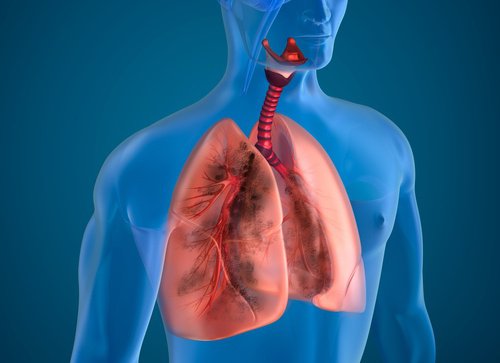

오늘은 흡연자의 폐를 정화하는 천연 재료를 소개한다. 폐는 삶에서 꼭 필요한 역할을 수행한다. 우리가 살아가기 위해서 필요한 산소를 제공하고 호흡을 통해서 이산화탄소를 배출하는 역할이다. 또한 해로운 환경요인들을 걸러내고 특정 질환이 발병하는 것을 막는 호흡기 기능을 하고 있다.

하지만 폐는 복잡하고도 섬세한 장기이기 때문에, 때때로 폐의 건강이 나빠지면 필요한 수준으로 그 역할을 수행하지 못하게 된다. 이런 현상은 특히 폐를 독소와 다른 건강에 해로운 성분에 노출시키는 담배에 중독된 사람들에게서 발견된다.

흡연 습관은 호흡기 질환과 암 같은 다른 만성 질환의 시작의 가장 흔한 원인 중 하나이다. 따라서 흡연자들이 이 습관을 끊고 라이프스타일을 개선하고 폐를 정화하도록 노력하는 것이 꼭 필요하다.

이런 의미에서 오늘은 독소를 배출함으로써 흡연자의 폐를 정화하는 데 도움을 주는 음식 몇 가지를 소개한다!